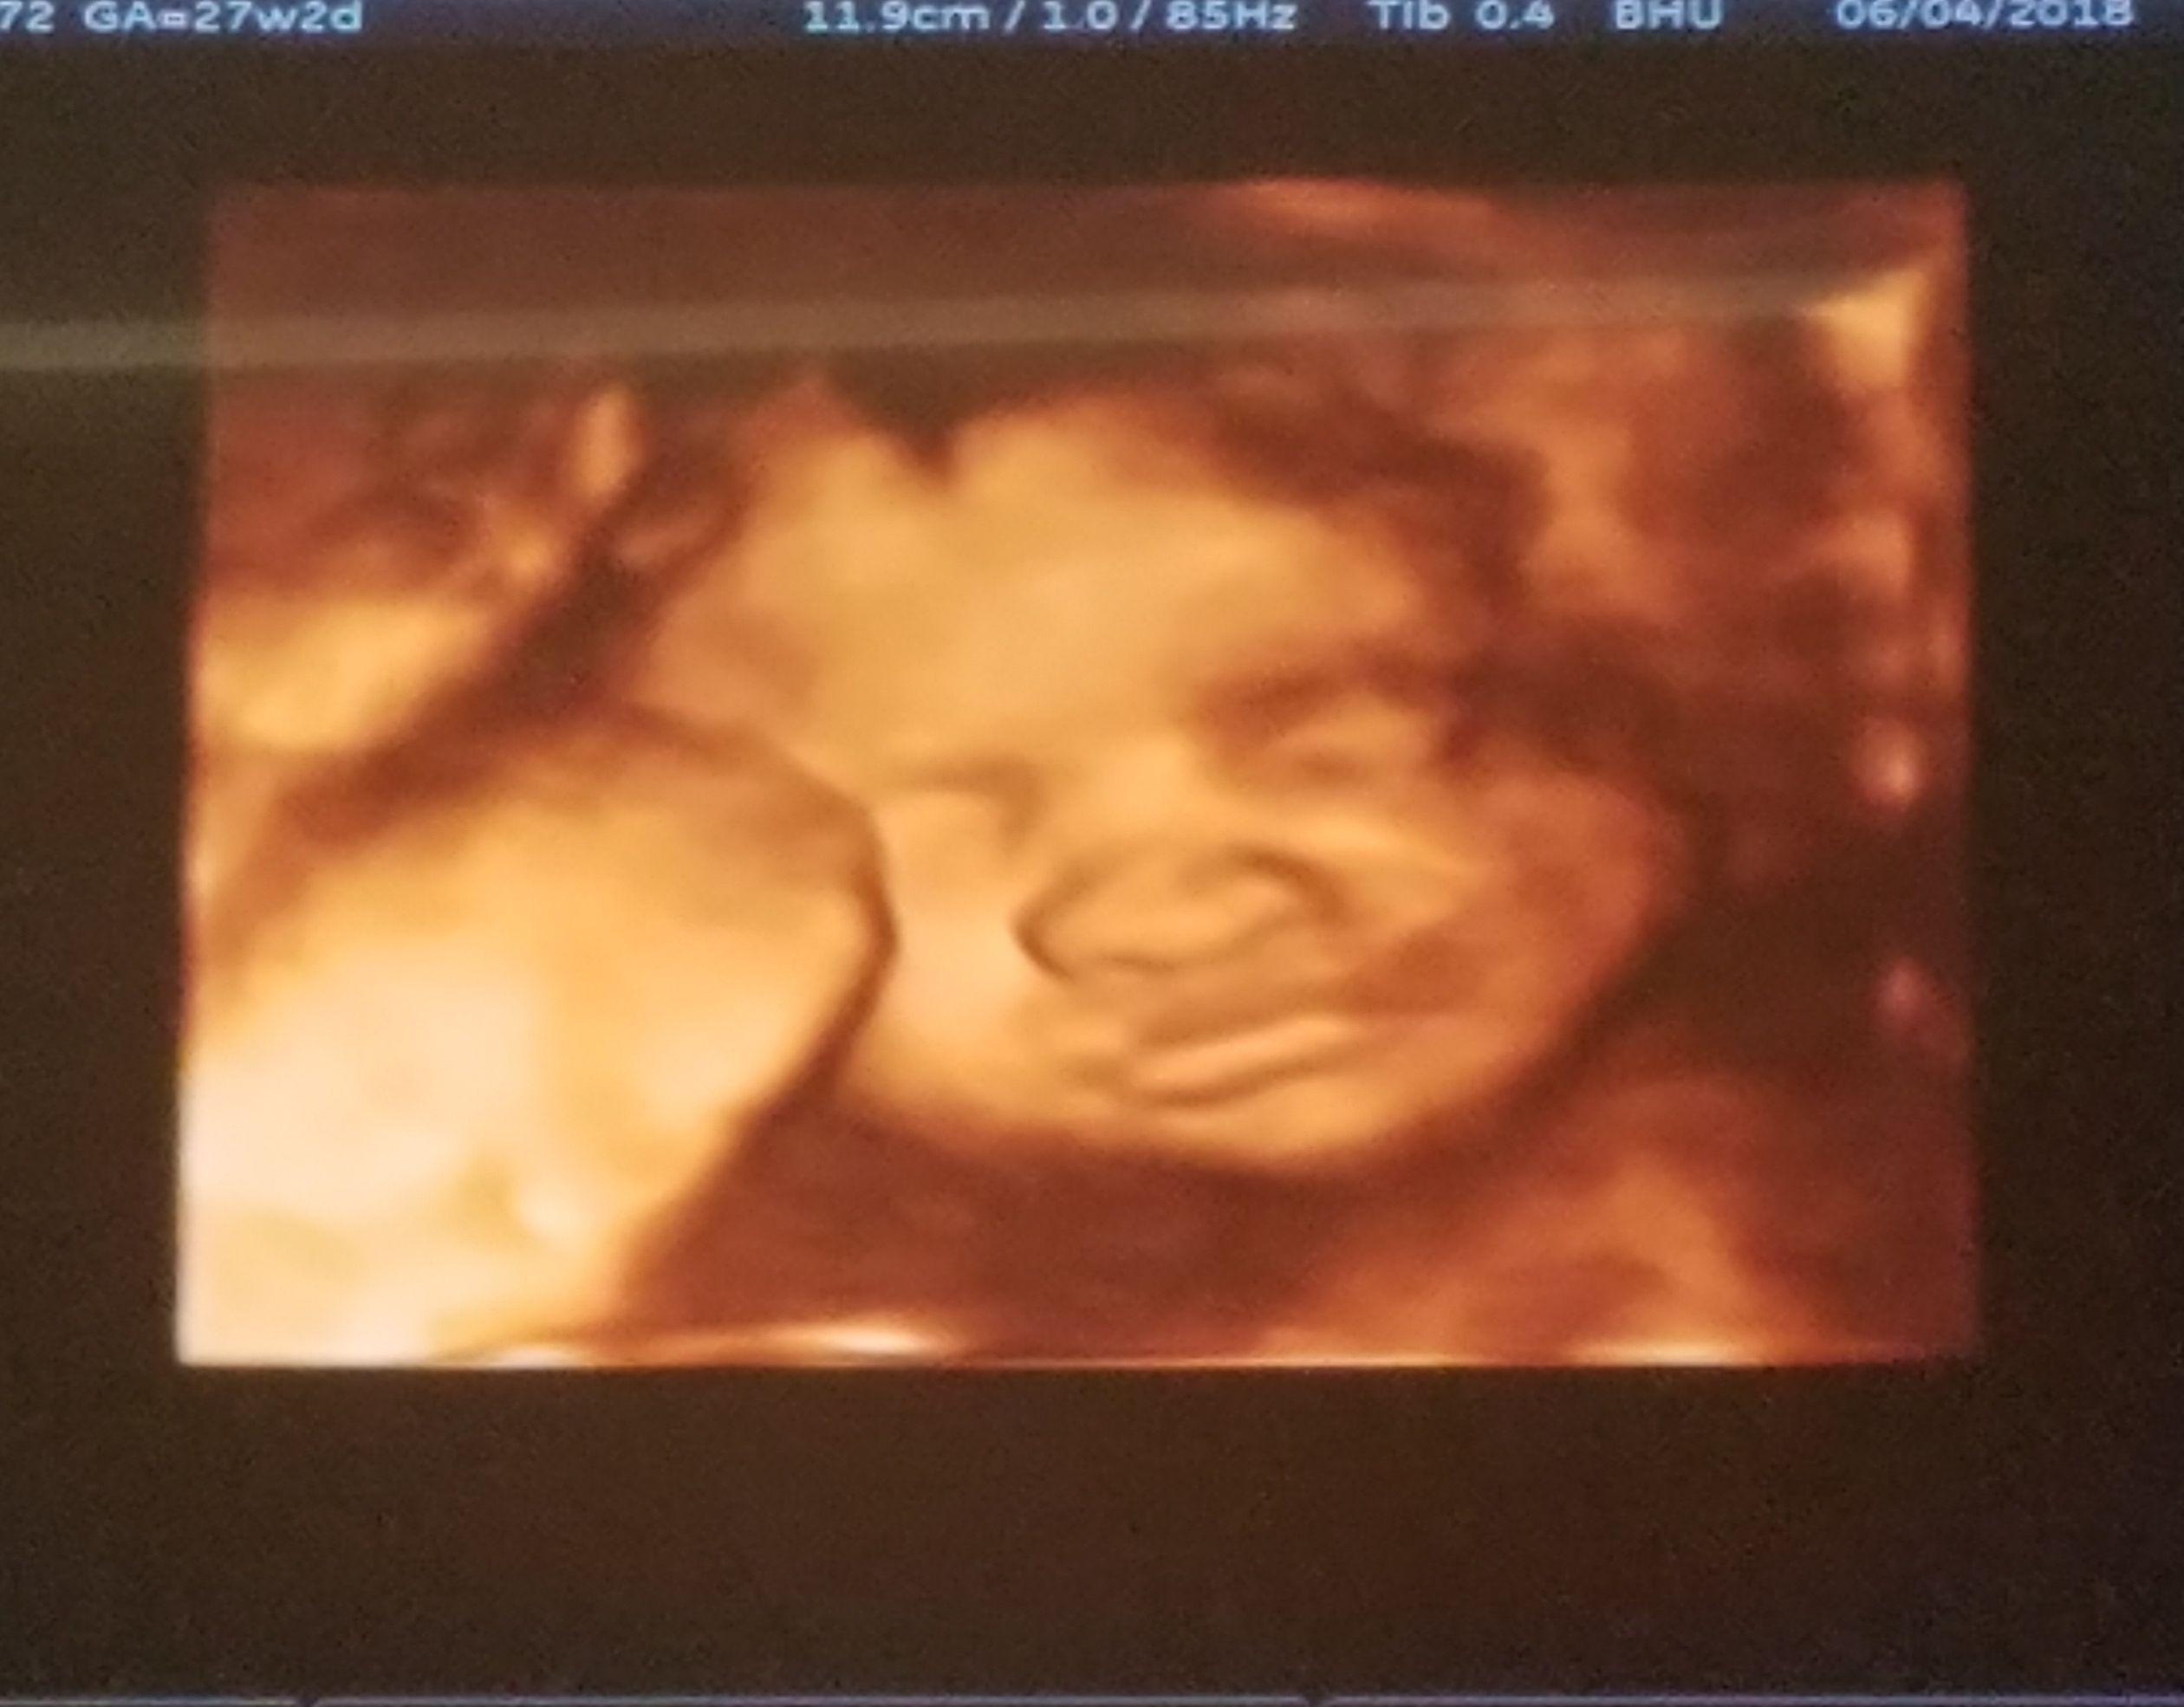

Sam Stasinowsky shares how at her 22-week ultrasound all she really wanted to know was if she was expecting a baby boy or girl.

But when the sonographer was silent she knew something was terribly wrong.

Her little girl was diagnosed with a major heart defect.

Little Sophie was born with her major heart arteries reversed and needed immediate surgery. A surgery with a 90% success rate.